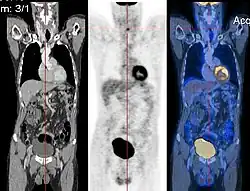

Image registration is a process that searches for the correct alignment of images.[21][22][23][24] In the simplest case, two images are aligned. Typically, one image is treated as the target image and the other is treated as a source image; the source image is transformed to match the target image. The optimization procedure updates the transformation of the source image based on a similarity value that evaluates the current quality of the alignment. This iterative procedure is repeated until a (local) optimum is found. An example is the registration of CT and PET images to combine structural and metabolic information (see figure).

- Combining complementary information from different imaging modalities. An example is the fusion of anatomical and functional information. Since the size and shape of structures vary across modalities, it is more challenging to evaluate the alignment quality. This has led to the use of similarity measures such as mutual information.[25]